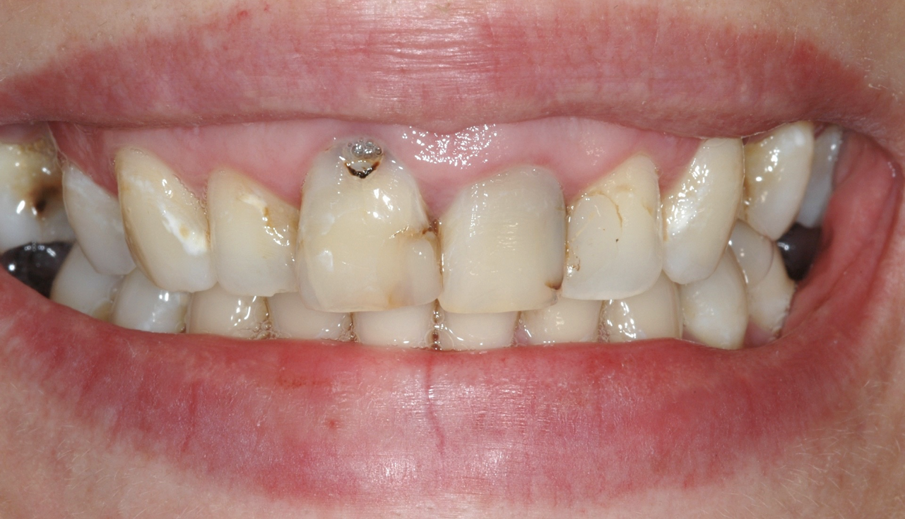

Una giovane paziente di 31 anni, si presenta al mio studio per risolvere l’inestetismo provocato dalla presenza di carie al colletto dell’11, e asimmerie delle parabole. Gli elementi frontali dal 12 al 22 presentavano inoltre diverse carie della corona clinica e contestualmente delle radici trattate in modo incongruo, tanto da provocare delle lesioni endodontiche molto ampie.

Figg. 1, 2 - Situazione iniziale.